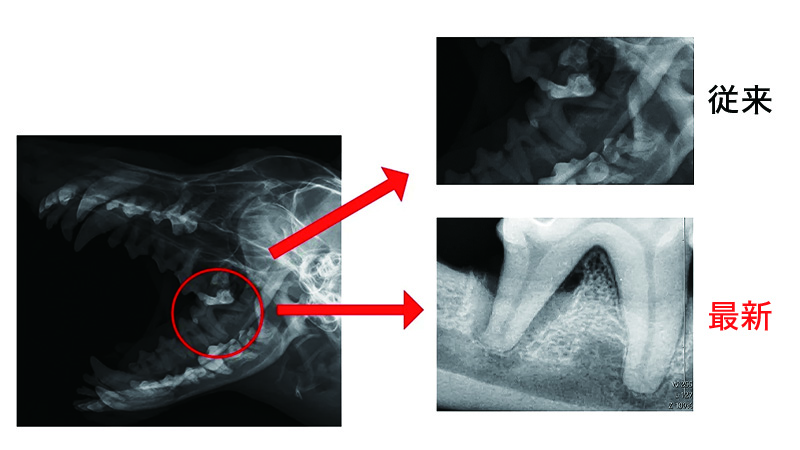

歯科レントゲン

従来のレントゲン検査よりも鮮明に細部まではの状態を観察することができます。